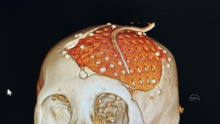

除了PEEK 钛网 本次用了超高分子量聚乙烯 颅骨修补

脑血管-烟雾病